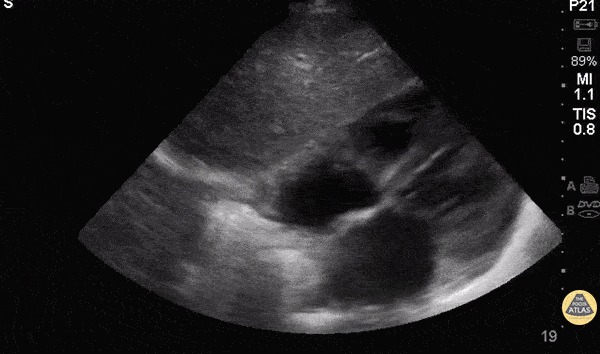

Normal Cardiac Anatomy - Subxiphoid / Subcostal - Normal Anatomy

The most superficial structure we see is the liver. Immediately deep to that we see the heart separated from the liver by the diaphragm. Closest to the liver is the right atrium, tricuspid valve, right ventricle. Deeper to that, we see the left atrium, mitral valve, and left ventricle. Hannah Kopinski - MS4, Dr. Lindsay Davis - NYU/Bellevue Department of Emergency Ultrasound, Dr. Matthew Riscinti - Kings County Emergency Medicine